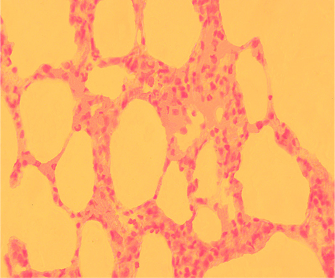

PREVENTION OF OSTEORESORPTION

the introduction of allogenic HAP on the day of surgery

Color: hematoxylin and eosin. Increase: 100

Bone tissue remodeling